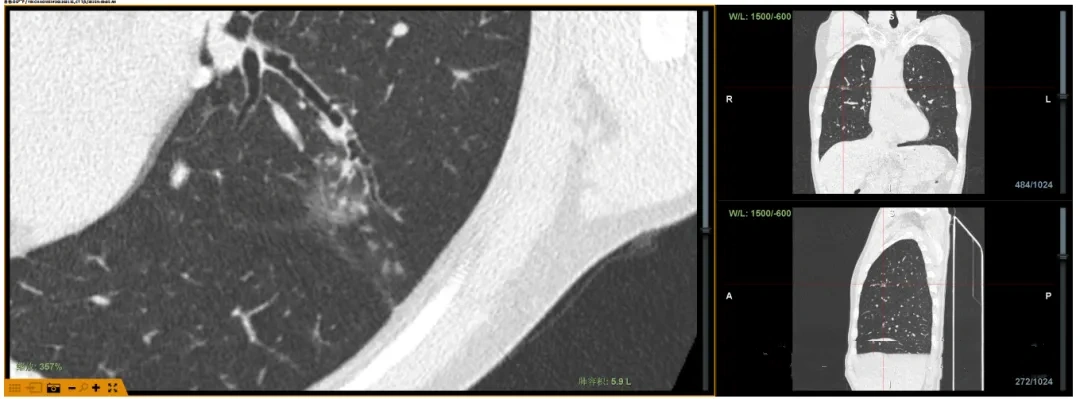

Lungpro全肺导航系统术前规划

1. Lungpro全肺导航系统:犹如为医生安装了“GPS肺内导航仪”,它能基于患者CT数据重建精细的支气管树3D地图,规划抵达肺外周“隐秘角落”结节的最优路径,避开重要血管,极大提升操作精准度。